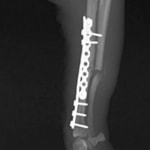

脛骨骨折 : 症例1 | 症例2 | 症例3 | 症例4 | 症例5

当院ではAdvanced Locking plate system(ALPS)と、Locking compression plate system(LCPS)という骨接合法で骨折症例の治療を行っています。

Locking Compression Plate

LCPは、スクリュー(ネジ)とプレート(金属の板)をロックする特殊な構造により骨折部位を固定する新しい世代のプレートシステムです。ひとつのホールでロッキングスクリューとスタンダードスクリューの使用を選択できるユニークな構造をしているため、骨折断端間の圧迫を目的とした従来型プレート固定法に加え、高い角度安定性を有するロッキングスクリューを用いた固定法の選択が可能です。従来のプレートシステムでは困難だった部分の骨折や癒合不全の症例に高い治療効果をもたらします。